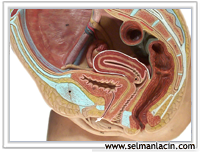

İnsan yaşamının en başında embriyoda başlıca 3 hücre tabakası bulunur. Bu tabakalar farklılaşarak değişik hücre ve doku gruplarını ve organları oluştururlar. Bu tabakalara germ hücre tabakaları adı verilir.